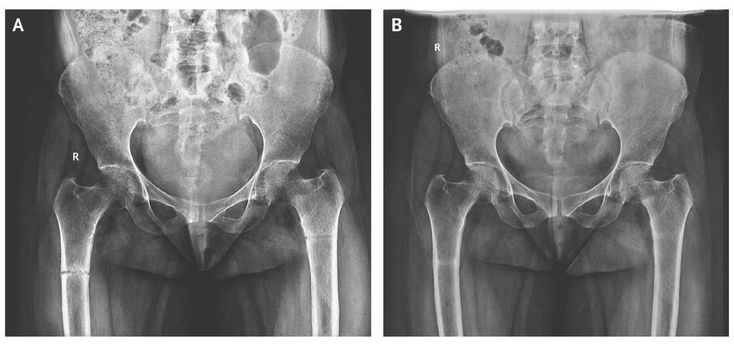

A 45-year-old woman presented with a 3-month history of generalized body pains that were nonresponsive to analgesic agents. Along with low back pain, she had progressive difficulty in getting up from sitting and supine positions and in walking. There was no history of trauma or any medication intake. She is an orthodox Muslim woman who wears a black veil outdoors and is completely covered, with little exposure to the sun, even in her courtyard. On examination, she had a waddling gait with painful movements of both thighs. The serum calcium level was 8.4 mg per deciliter (2.1 mmol per liter) (reference range, 8.0 to 10.4 mg per deciliter [2.0 to 2.6 mmol per liter]), the phosphate level 1.5 mg per deciliter (0.5 mmol per liter) (reference range, 2.5 to 4.5 mg per deciliter [0.8 to 1.5 mmol per liter]), the alkaline phosphatase level 916 U per liter (reference range, 30 to 120), and the 25-hydroxyvitamin D level 9 nmol per liter (reference range, 18 to 100). An anteroposterior radiograph of the pelvis showed an undisplaced transverse fracture of the shaft of both femurs (Panel A). The patient was treated with therapeutic doses of calcium and vitamin D supplements. After 3 weeks, her symptoms had improved substantially, and she walked with minimal pain. Blood tests showed an increase in the phosphate level to 3.0 mg per deciliter (1.0 mmol per liter) and a decrease in the alkaline phosphatase level to 418 U per liter. A follow-up radiograph showed healed fractures (Panel B). Patients with osteomalacia may present with generalized osteopenia. A radiographic study may show cortical stress fractures, often called Looser zones or pseudofractures, which are seen as bilateral, symmetric, radiolucent lines in the bone cortex perpendicular to the long axis. Looser zones contain fibrous tissue and poorly mineralized callus and are often found on the ribs, the femoral neck, the pubic rami, and the axillary margins of the scapulae.